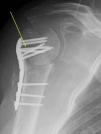

Case PresentationThe patient was a 54-year-old male with liver disease, allergic to penicillin, presenting a proximal humeral fracture with a cervicodiaphysal angle of 80° and a trochiter ascent of 11mm. Pl osteosynthesis was performed with a Philos plate (Synthes®) (Fig. 1). The patient began rehabilitation, with a limited arc (60° of active abduction and 50° of anterior active flexion), fever and wound seroma (ultrasound size: 25mm×12mm), at 2 months and 22 days after the intervention, requiring 2 surgical debridements and the taking of cultures and antibiograms.